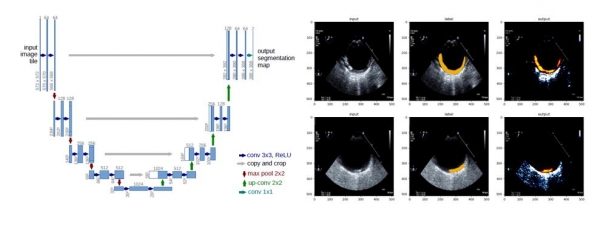

연구팀은 머신러닝의 다양한 기법 중 오토엔코더(Autoencoder)와 유넷(U-net)모델을 대동맥벽의 초음파 영상 판별에 적용했다. 대동맥벽을 초음파 영상으로 판별하면 뇌졸중의 원인으로 떠오르고 있는 대동맥 동맥경화성 플라크의 상태를 확인할 수 있다.